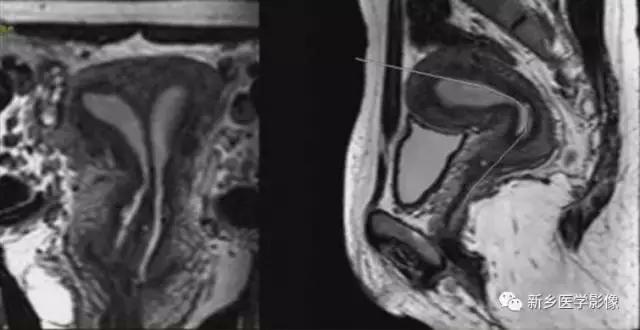

左图:完全双角子宫,分隔延伸至宫颈内口或外口。

右图:部分双角子宫,分隔局限于宫底。

子宫上部不融合,下部及宫颈融合。宫底凹陷>1cm,双侧宫角分离。宫颈有或无分隔,25%伴有纵隔。

双角子宫:不完全型,宫底凹陷,上部子宫不融合,子宫纵隔未达宫颈内口水平。

双角子宫:完全型